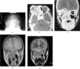

Ethmoid sinus cancer

The ethmoid sinuses or ethmoid air cells of the ethmoid bone are one of the four paired paranasal sinuses. The cells are variable in both size and number in the lateral mass of each of the ethmoid bones and cannot be palpated during an extraoral examination. [Source: Wikipedia ]